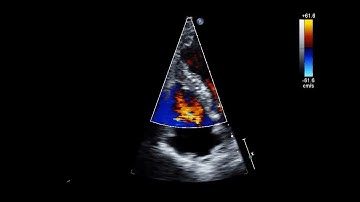

Post-MI VSD repair with VSD occluder